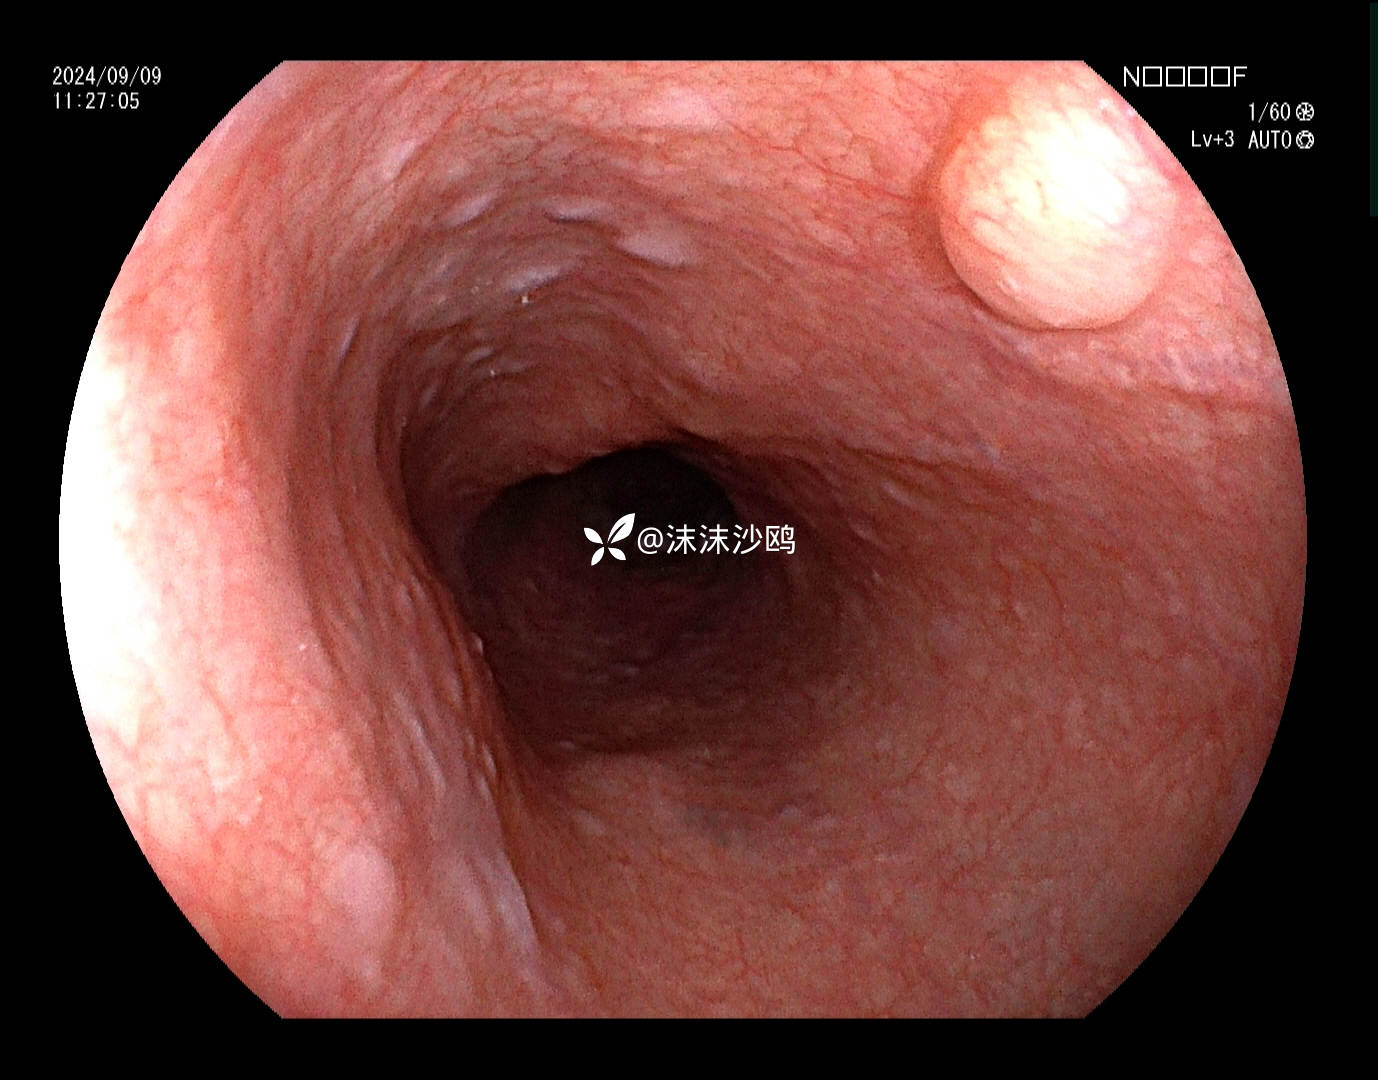

老年男性,腹胀不适门诊行普通胃镜检查。距门齿30cm见片状粘膜粗糙发红,呈0-II b型病灶。

白光

上段食管见粘膜下隆起,考虑平滑肌瘤?

距门齿30cm见片状粘膜粗糙发红,大小约2cm,形态0-II b型